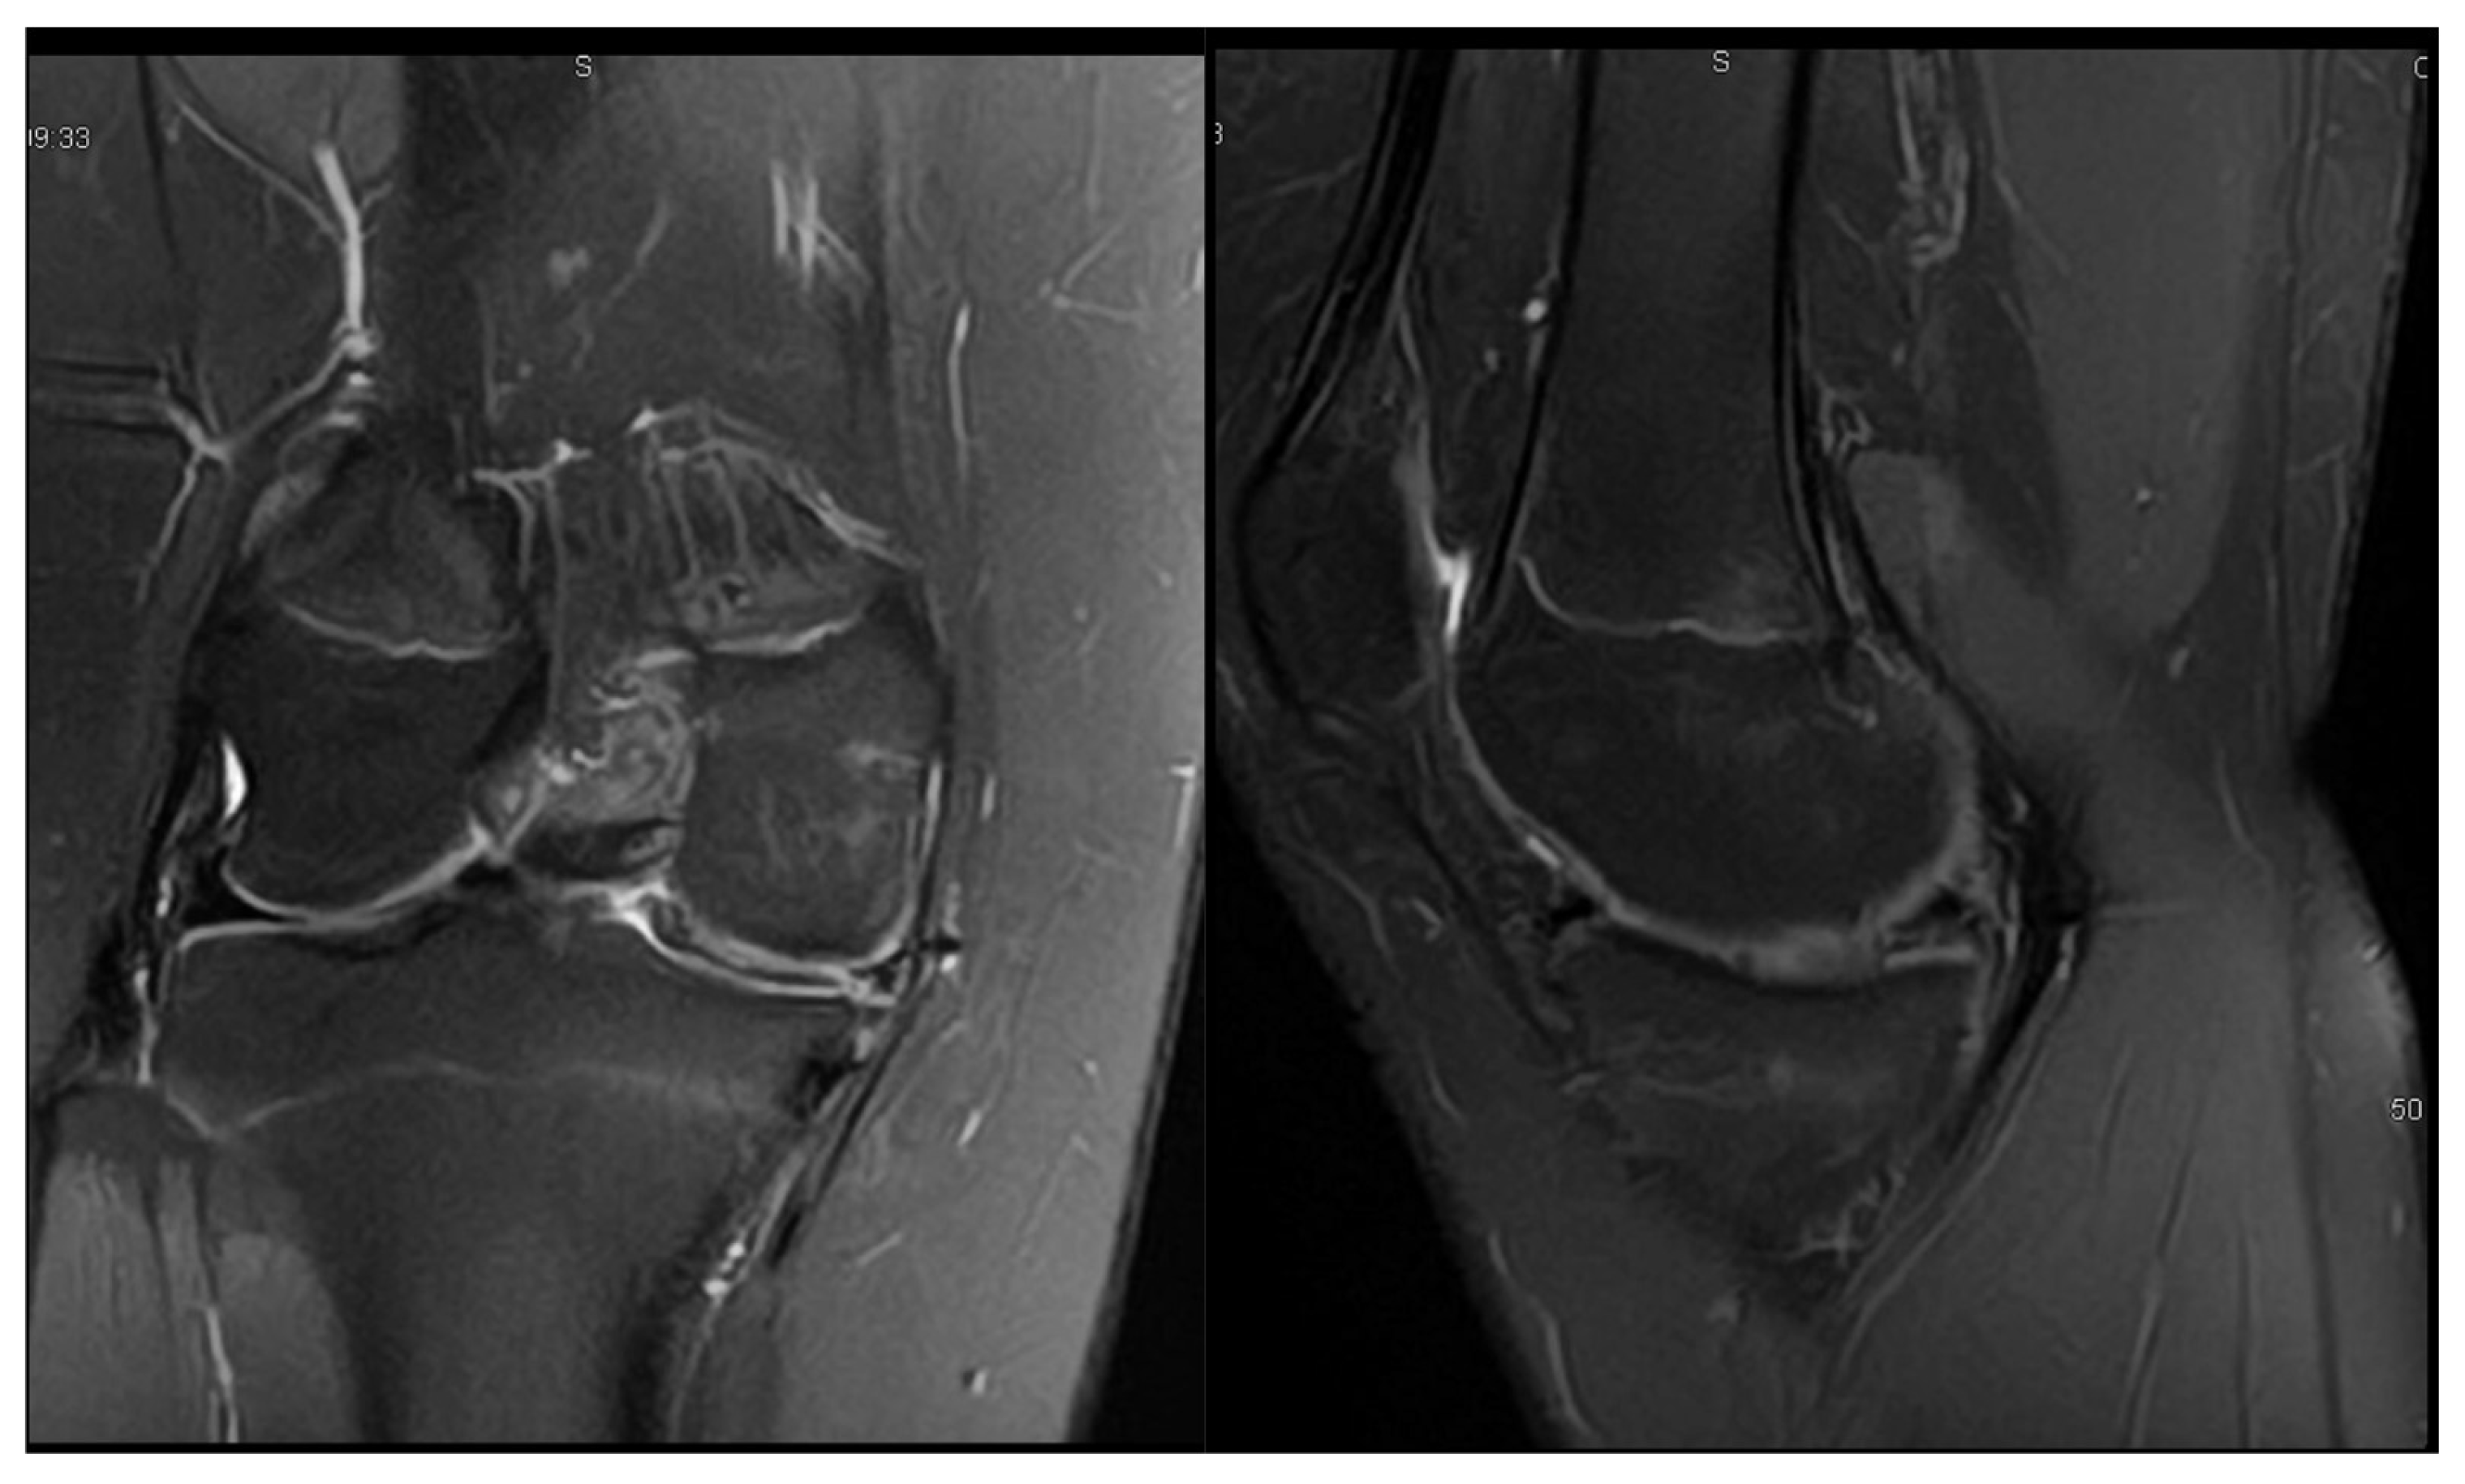

3.1. Case 1—P.E.

| P.E. | 12 | Bilateral (symptomatic right) | Chronic pain, effusion, normal ROM | None | 3 surgeries: partial meniscectomy (12 years), suture for horizontal tear (13 years), suture for radial tear (14 years) | 1 year after third surgery: symptom-free, resumed school sports |